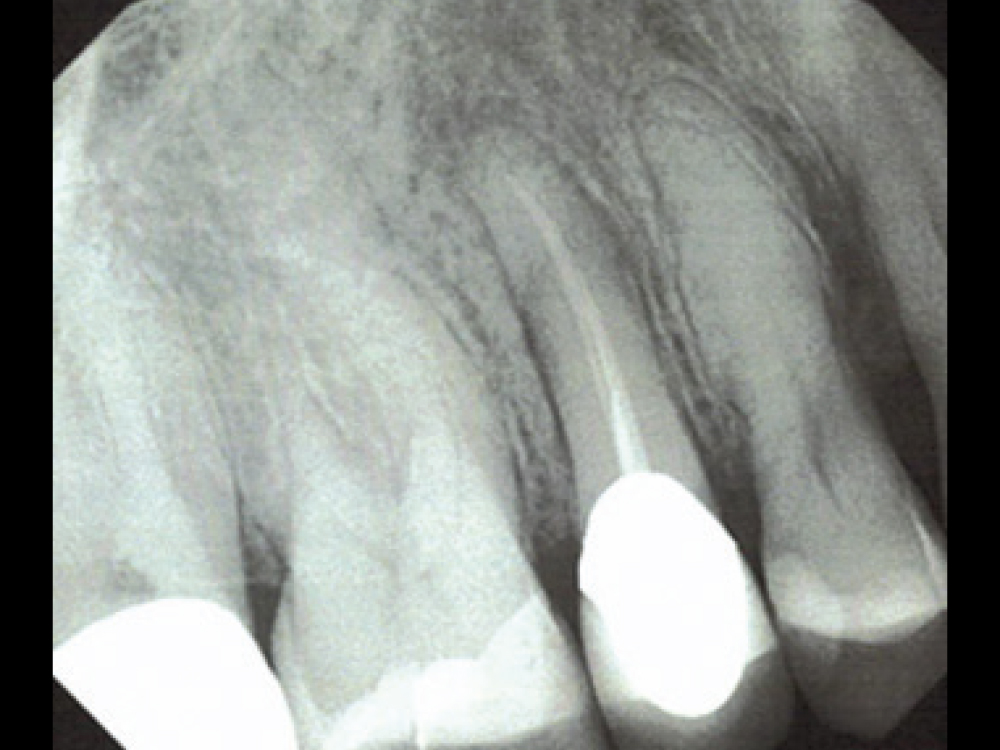

Extraction Site by Fenestration Case Pt2

Extraction Site by Fenestration Case Pt3

Extraction Site by Fenestration Cast Pt4

Extraction Site by Fenestration Cast Pt5

In this case example, an implant was immediately placed into an extraction site compromised by a fenestration. By utilizing the appropriate diagnostic, surgical and bone grafting techniques, a predictable restoration was delivered for the patient, and abundant bone volume was evident around the Hahn Tapered Implant.